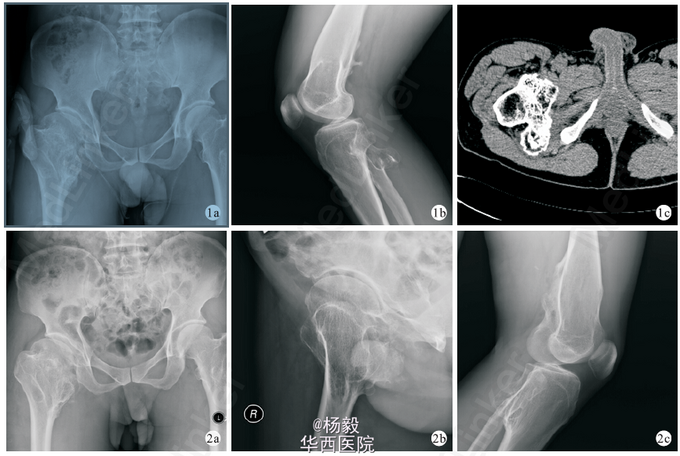

多发性骨软骨瘤(MO)是指放射影像学可显示至少2 处长骨干骺端有骨软骨瘤。多发性骨软骨瘤可导致一系列的并发症如疼痛、畸形、局部血管、神经等的压迫、骨折、恶变等。MO 病因不 明,原来认为MO 是一种常染色体显性遗传,侵犯骨组织的一种疾病,现有研究发现硫酸乙酰肝素(HS)对所有组织具有重要的生物性,HS 缺失可导致很多的组织组织学改变,涉及到白细胞、肾脏、神经脊细胞、眼睛 及内皮细胞,推断MO 可能是累及全身组织的一组临床综合征,因为其他系统临床症状轻微,以致未发现相应的临床表现。 参考文献:[1]刘东,叶永杰,银毅,陈刚. 多发性骨软骨瘤病例分析[J]. 华西医学,2014,11:2102-2104.